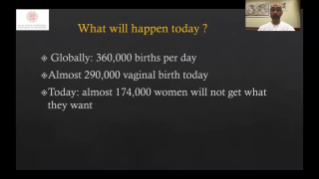

Con la tecnologĂa de la avanzada plataforma ZST+, las soluciones inteligentes completas de la serie Nuewa estĂĄn dise?adas especialmente para mejorar la salud de las mujeres durante el perĂodo previo al embarazo, el embarazo y la recuperaciĂłn en el posparto, con el fin de brindar diagnĂłsticos integrales y eficientes para enfrentar desafĂos clĂnicos cada vez mĂĄs exigentes.